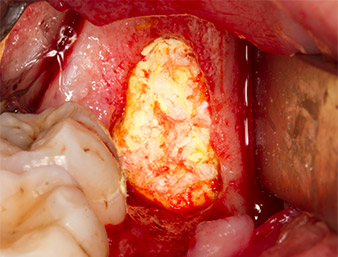

To obtain autogenous material for subsequent wound treatment, healthy bone chips were harvested from the surroundings of the root remnant with a piezo surgical instrument (Piezomed B5) (Fig. 5).

Piezomed B5

Fig. 5: Bone in the region of the alveole is lifted with a chisel-shaped piezo surgical instrument (Piezomed B5). This bone is used as autologous augmentation material after removal of the root remnant (cf. Fig. 13 and 14).

The autogenous tissue was removed with the scraper-shaped section of the working part of the instrument and stored in a physiological saline solution until further use (cf. Fig. 13).

To expose the root remnant with as little trauma as possible to the tissue, a further instrument was used (Piezomed S2) that is primarily indicated for preparing the lateral window in augmentations of the sinus floor. The diamond-coated ball was additionally used to smooth sharp bone edges (Fig. 6 and 7). All the Piezomed attachments were used with the relevant automatic default setting without booster function.

Piezomed S2

Fig. 6: The root remnant is carefully exposed with a diamond-coated spherical instrument (Piezomed S2), bone edges are smoothed.